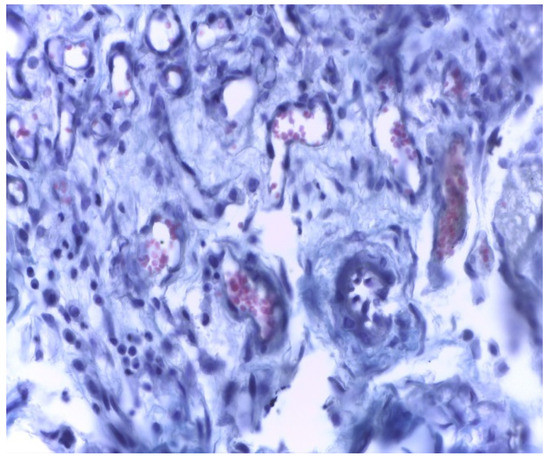

In group B, the local reaction was slightly reduced in intensity, with the necrotic area being much smaller compared to group A. The present cells, neutrophils, macrophages, and fibroblasts were fewer in number. The implanted material was partially reabsorbing, as shown by the migration of neutrophils and macrophages to the implantation site (Figure 7 and Figure 8).

Figure 7. Group B. Moderate inflammation and mild congestive subcutaneous connective tissue in rabbits at 7 days after implantation. Col. Trichrome Masson, ×400.

Applsci 11 06519 g007

Figure 8. Moderate necrosis area with pockets of implanted material and moderate leukocyte influx. Partial resorption of the implant material. Subcutaneous tissue, 7 days after implantation. Col. Trichrome Masson, ×200.